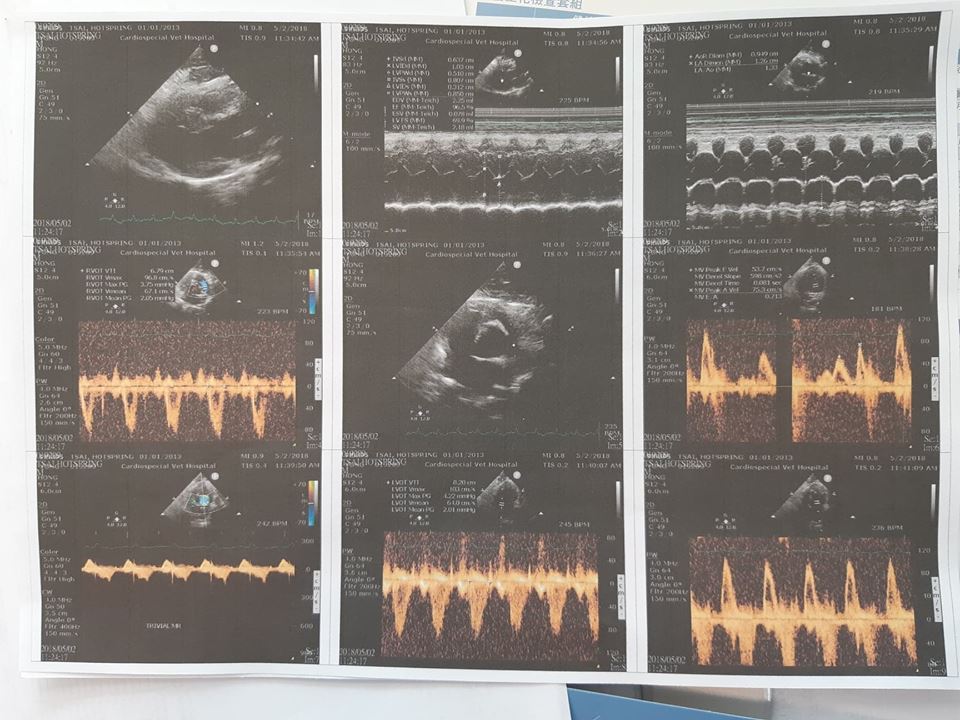

溫泉每六個月一次的定期回診,包含了全套血檢,心臟超音波,心電圖以及照x光,從四月份的心跳呼吸紀錄表上顯示,溫泉的心跳最高200最低132,醫生認為數據落差過大,並囑咐要盡量避開會讓他情緒激動的事物。

檢查完確認溫泉的心臟形狀大小適中,心肌也沒有特別肥厚,因此維持舊有用藥劑量。另針對溫泉最近眼睛淚水顏色變深,由於並未見到黃綠色分泌物(有感染),建議由眼科醫師判斷是否為睫毛倒插所致或可能是其他眼疾。